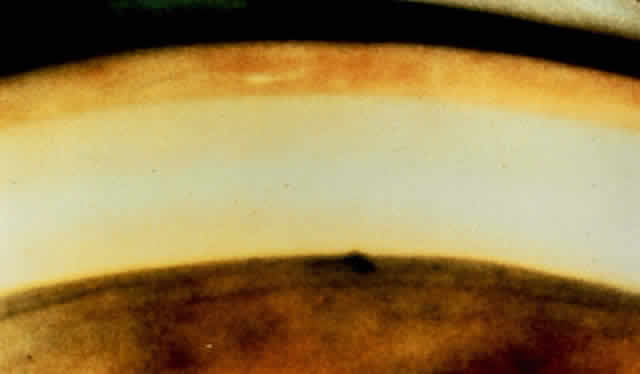

On early examination, the cardinal sign of primary acute angle-closure glaucoma is present: a fixed mid-dilated pupil. There is profound reduction in central visual acuity. Photophobia and conjunctival hyperemia are striking external findings (Fig. 6). Intraocular pressure usually exceeds 40 mmHg and may be as high as 70 or 80 mmHg during the attack. On biomicroscopy, perilimbal hyperemia with a ciliary flush is accompanied by peripheral conjunctival and episcleral congestion. The peripheral iris bulges anteriorly and comes in close contact with the peripheral corneal endothelium for 360 degrees. Early microcystic epithelial corneal edema evolves to stromal edema. The anterior chamber appears shallow but formed centrally with cells, pigment and aqueous flare. Sustained high intraocular pressure affects the iris sphincter muscle, as well as its blood supply.33 Ischemia of sectors of the iris develop, probably due to compression of nutrient radial iris vessels causing infarction of the compromised iris and possibly also the ciliary body. This results in the release of debris and proteins, causing an aseptic anterior uveitis.

Fig. 6. A most reliable sign in angle-closure glaucoma is the unreactive pupil in the mid-dilation. Conjunctival and ciliary vascular engorgement, as well as epithelial corneal edema, is present. In this eye, no atrophy of the iris is visible, but the iris sphincter is unreactive, presumably as a result of ischemia caused by the elevated intraocular pressure. If high pressure is relieved before permanent atrophy of the iris occurs, the pupil will again become reactive. (Courtesy of Ayerst Laboratories and Dr. H. Saul Sugar)